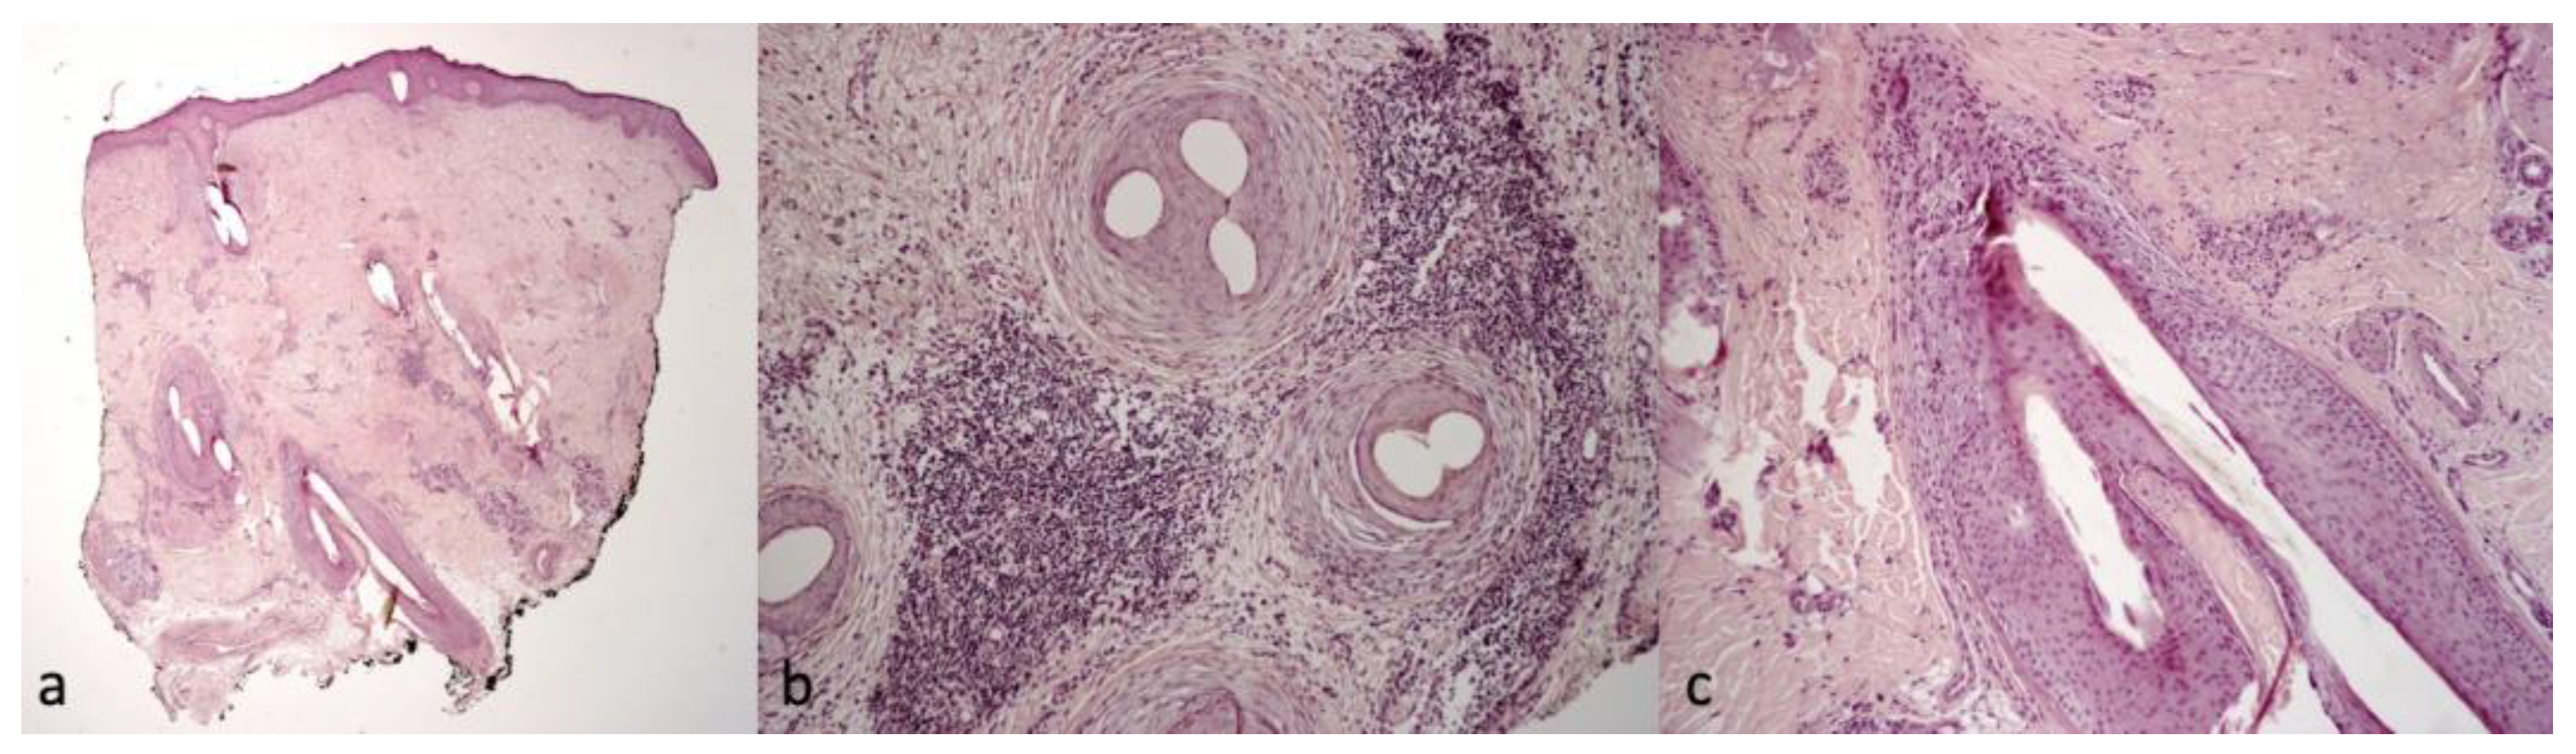

Figure 5.

Histological findings of Patients 2 and 3, showing diffuse fibrosis, focal perifollicular suppurative, and mixed infiltrate in the dermis. “Tufted folliculitis” (a) 2× magnification, H&E and (b,c) 20× magnification, H&E.